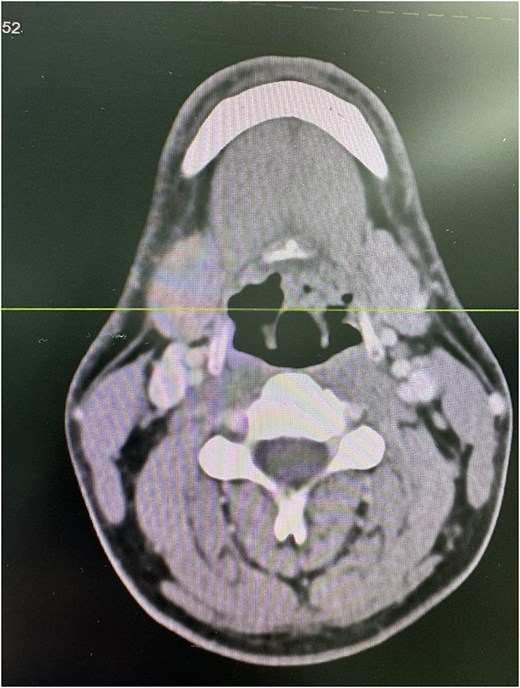

A computed tomography (CT) scan of the neck with intravenous contrast showed a tiny non-enhancing nodule in the posterior aspect of the upper end of the left aryepiglottic fold measuring 4 × 4 mm, with asymmetry of the vallecula and shallowness on the left side, which was likely due to the extension of the lingual tonsils (Fig. 2).

Axial CT scan of the neck with intravenous contrast demonstrating a 4 × 4 mm non-enhancing nodule (arrow) in the posterior aspect of the upper end of the left aryepiglottic fold. Asymmetry of the vallecula is noted with shallowness on the left side, likely due to the extension of the lingual tonsils.